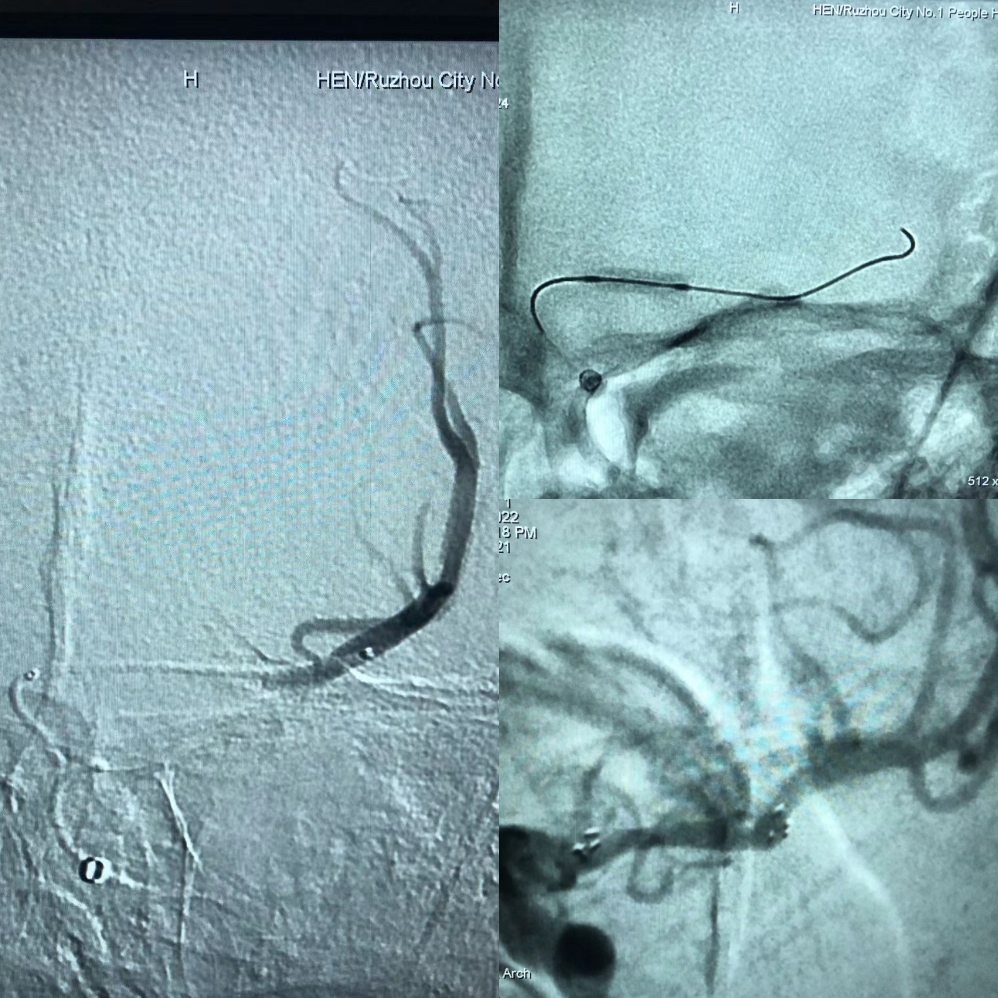

造影:左侧大脑中动脉闭塞,左侧椎动脉闭塞。

Synchro200mm微导丝配合Rebar18微导管穿越闭塞段,经Navien及微导管造影提示闭塞段位于左侧大脑中动脉中段,闭塞段很短,推测血栓负荷量极少。

送入300mmSynchro微导丝,Gateway2.5*9mm球囊扩张后,观察血流,出现弹性回缩。再次扩张后,撤出球囊,交换PLUS导管,送入Enterprise4.0*23mm支架,顺利释放,血流维持可,轻度残余狭窄。

术后造影,血流通畅,TICI分级3级。